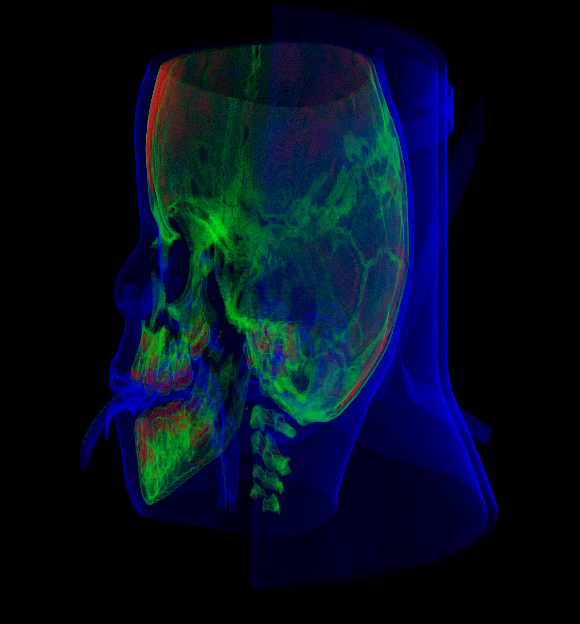

In the figures throughout this paper, we used the “Baby Head” data set available from the volume library of Stefan Roettger222http://schorsch.efi.fh-nuernberg.de/data/volume/.

The task for these two test users was to reproduce a visualization result for the “Baby Head” data set, starting from a default transfer function. The predefined visualization result was produced with a transfer function consisting of three peaks that separate the skeleton (green), the teeth (red), and the skin (blue). See Fig. 7.

The experienced test user was able to solve the task in less than half a minute with good results, shown in Fig. 7. After an introduction to controller usage and button configuration, the inexperienced user was able to achieve a satisfying result, shown in Fig. 7, in approximately one minute.